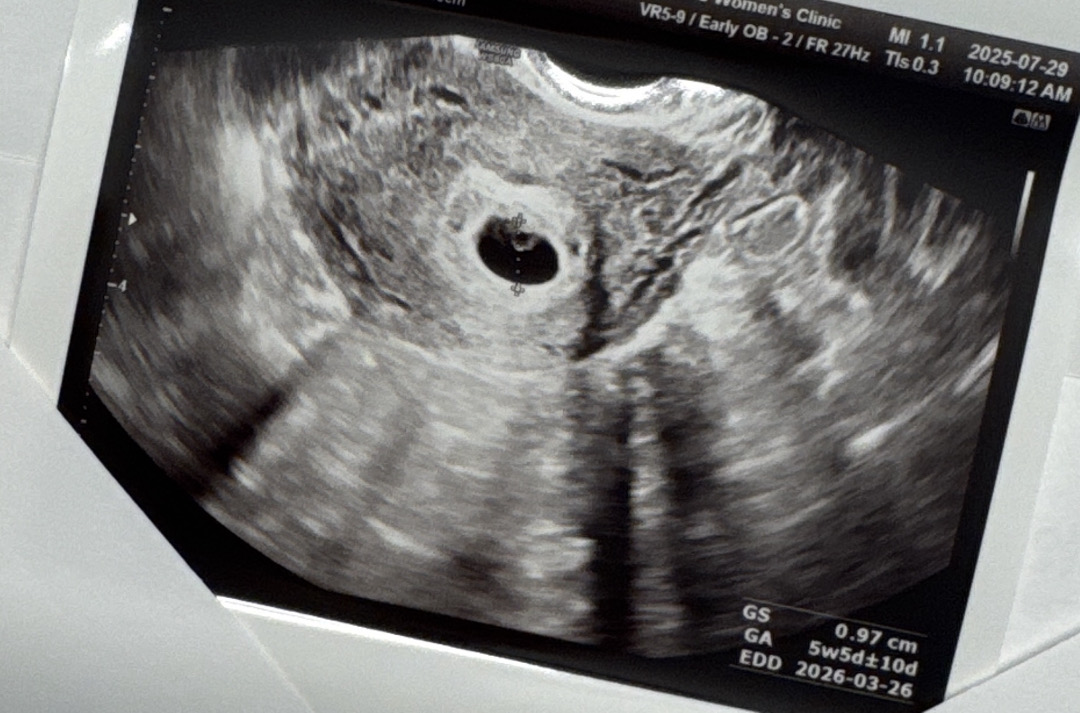

6주2일이라고 생각했는데 5주5일추정 난황까지 보고 왔어요,,! 심장소리랑 아기는 언제 보는걸까용 ㅎ ,,,,,, ㅠㅠㅠ 2주뒤에 오라고 하셨는데 시간 진짜 안가요,,,!! ㅎㅎ

저도 막생리 기준 6주생각 하고 갔는데,초음파 상으로는 5주 반정도 됐대요 이번주 금요일에 심장 초음파 들으러 가요 8주 좀 넘어서 9주 정도 되어야 하리보 볼수 있다고 그러더라고요 시간이 참 안가는거 같아요